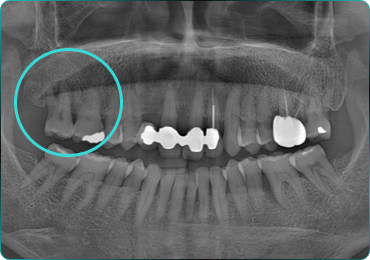

뼈와 임플란트를 한번에!

뼈플란트, 그 결과의 차이를 경험해보세요!

67세 여성

Before